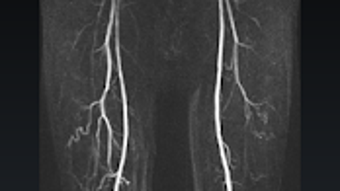

O aplicativo oferece uma interface intuitiva, permitindo que os usuários naveguem facilmente por diferentes seções e conteúdos. Com uma abordagem educativa, o Radiological Anatomy For FRCR1 inclui ilustrações e descrições detalhadas, favorecendo a assimilação do conhecimento. É uma opção acessível e prática para aqueles que desejam aprofundar seus conhecimentos em anatomia radiológica, tornando-se um recurso indispensável para estudantes e profissionais da saúde.